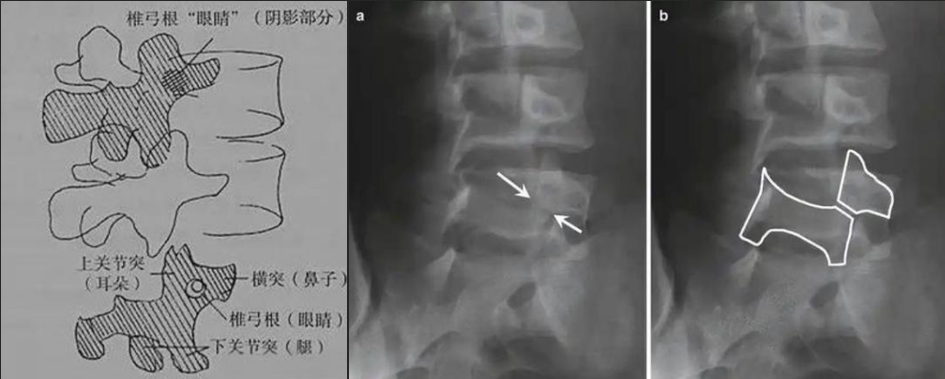

腰椎斜位片看什么?

如果說(shuō)腰椎正側(cè)位片是常規(guī)檢查體位,那么腰椎斜位片就是給腰椎的某個(gè)零件一張?zhí)貙?xiě)鏡頭,這個(gè)特殊且關(guān)鍵的部位就是椎弓根峽部。

圖a和圖b 腰椎斜位:狗脖“戴項(xiàng)圈征”,診斷椎體椎弓峽部裂

椎弓根峽部是椎體后部椎弓上最狹窄、最薄弱、但應(yīng)力最集中的部位,在常規(guī)腰椎X線正側(cè)位上,因腰椎其他結(jié)構(gòu)的重疊顯示不清,但是在腰椎斜位上,能夠清楚完美地展現(xiàn)出來(lái),若其在斜位片上表現(xiàn)為不連續(xù),則可診斷為椎弓根峽部裂,即腰椎的關(guān)鍵承重部分的骨質(zhì)斷裂,這是導(dǎo)致青少年和運(yùn)動(dòng)員腰痛的主要原因。

在腰椎斜位片上,腰椎的附件結(jié)構(gòu)形成了一個(gè)經(jīng)典的“斯科蒂狗”圖案,其中“狗脖子”處即代表椎弓根峽部,若“狗脖子”上出現(xiàn)了一條透亮清晰的線,就像給狗戴了一條“項(xiàng)鏈”,即“戴項(xiàng)圈征”,這是診斷椎弓峽部裂的直接證據(jù)。